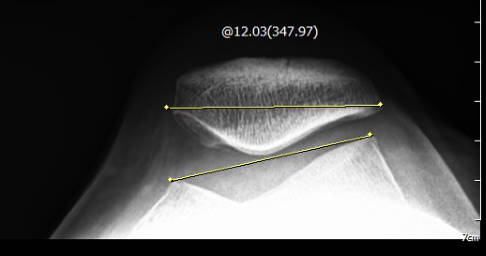

Zur Darstellung der Kniescheibe verwenden die Orthopäden der Gelenk-Klinik routinemäßig eine Defilee-Aufnahme. Dieses spezielle Röntgenbild zeigt das Ausmaß der seitlichen Abweichung der Kniescheibe aus der Mittellinie sowie eine Kippfehlstellung. Etwa sechs Wochen nach der lateralen Retinakulumverlängerung wird ein erneutes Röntgenbild angefertigt, um den korrigierten Sitz der Patella im Vergleich zum Ausgangsbefund darzustellen.